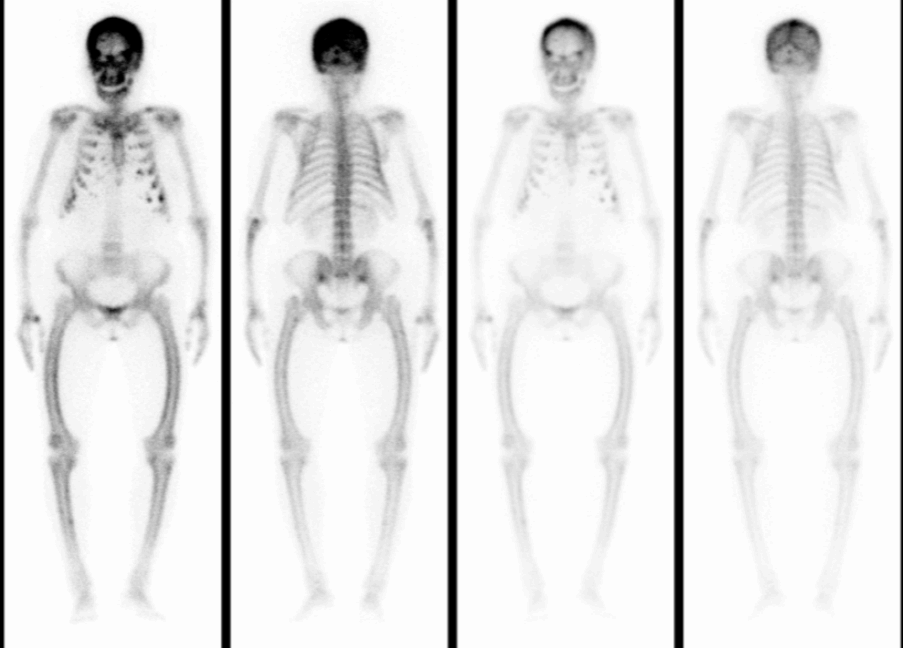

段阿姨,59岁,因腰背部疼痛1月,外院查CT示肋骨、骶骨骨质异常,骨转移?遂来核医学科行全身骨显像,判断是否是骨转移,图像(图1)如下:

全身骨骼显像剂分布弥漫性增强,肩胛骨、双侧部分肋骨、骶骨、右胫骨存在灶性显像剂异常浓聚,双肾及软组织本底显示不清,呈“超级骨显像”。

进一步的SPECT/CT断层融合显像(图2-4)显示:肋骨、肩胛骨、骶骨等灶性异常显像剂浓聚处伴骨质膨胀性骨质破坏。

通过全身显像,可以判断这些异常并非骨转移瘤所引起,而是一种代谢性骨病,结合SPECT/CT所示多发溶骨性骨质膨胀性破坏,考虑为甲状旁腺功能亢进所致代谢性骨病伴棕色瘤。为了进一步验证,段阿姨进行了血清电解质和甲状旁腺激素的测定,结果显示她的血清钙(3.14mmol/L)和甲状旁腺激素(1548pg/ml)水平明显增高,从而证实了甲状旁腺功能亢进症的诊断。段阿姨无慢性肾脏疾病、骨软化症、肠吸收不良综合征、维生素D缺乏等疾病的病史,因此诊断为原发性甲状旁腺功能亢进症。原发性甲状旁腺功能亢进症首选治疗方法为手术[1],而手术的成功主要取决于术前对功能亢进的甲状旁腺病变的精确定位,甲状旁腺显像则对识别功能亢进的甲状旁腺病变具有非常重要的意义[2]。